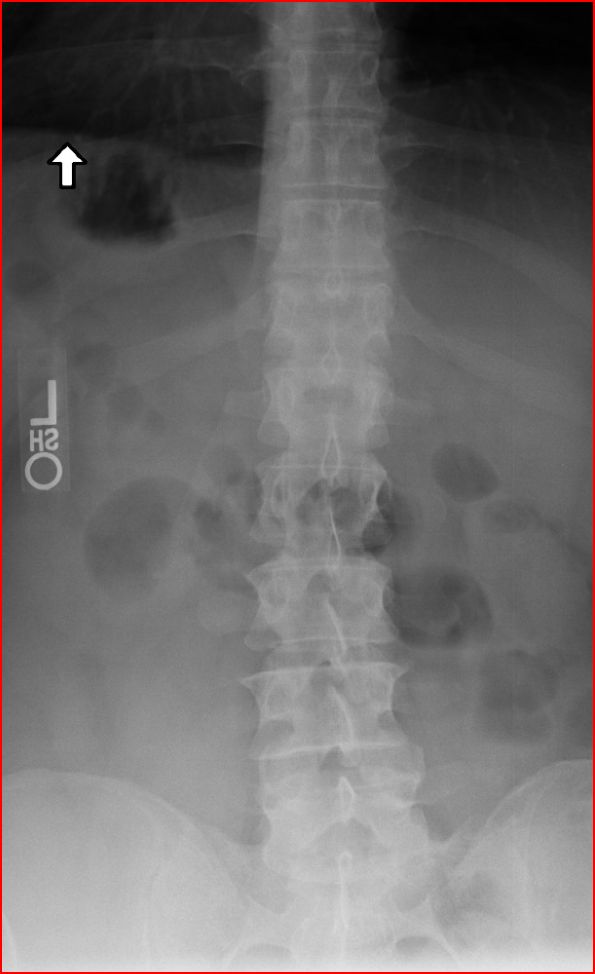

Here are a couple of shots from todays x-ray.

The pictures do not reflect the fracture as well as the film from the hospital. I’ll try to get that film and place it here.